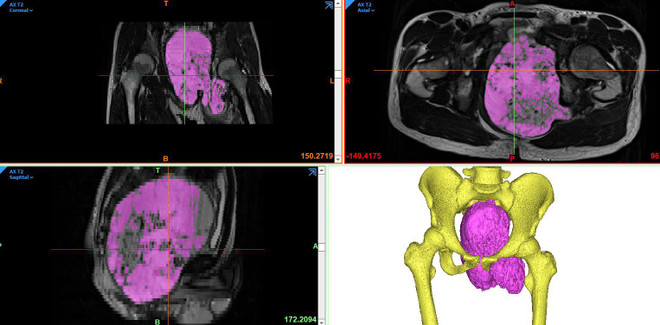

Bệnh nhân Đ.N.H.T được các bác sỹ tại Trung tâm Chấn thương Chỉnh hình và Y học thể thao Vinmec phát hiện khối u khổng lồ (chiều dài nhất trên 20 cm) nằm ở vị trí vùng tiểu khung sàn chậu rất hiếm gặp. Ước tính, mỗi năm tại Việt Nam chỉ có 5-10 ca, chiếm khoảng 5% các ca bệnh ung thư xương.

Giáo sư Trần Trung Dũng phân tích: “Khối ung thư xương khổng lồ như trong tiểu khung (giống như phụ nữ mang thai) đã gây chèn ép thần kinh toạ bên trái, khiến bệnh nhân tê bì teo cơ chân trái. Nếu không điều trị kịp thời không những chân trái mất chức năng mà ngay cả tính mạng cũng bị đe dọa. Do kích thước khối u tăng sẽ chèn ép và gây tắc hệ thống tiêu hoá hoặc tiết niệu. Vì vậy khối u cần phải loại bỏ sớm để giúp bệnh nhân phục hồi chức năng chi thể và tránh các biến chứng xa của hệ tiêu hoá và tiết niệu.”

Đại phẫu cho ca mắc ung thư xương với khối u trên 20cm hiếm gặp ảnh 2Phim chụp khối u khổng lồ của bệnh nhân. (Ảnh: PV/Vietnam+)

Phó Giáo sư Phạm Đức Huấn, Giám đốc Trung tâm Tiêu hóa-Gan mật-Tiết niệu của Bệnh viện cho hay với trường hợp này, bệnh nhân phải đối mặt với nguy cơ tử vong ngay trên bàn mổ bởi khối u được cung cấp bởi hệ thống mạch máu lớn và phức tạp, bệnh nhân có thể mất tới 10 lít máu. Việc tiếp cận khối u cũng là một thách thức do khối u đã chèn ép lên các cơ quan trọng yếu như hệ tiêu hóa, tiết niệu, cột sống, khung chậu, mạch máu. Trong quá trình phẫu thuật, nếu khối u chảy máu nhiều sẽ dẫn đến tình trạng không thể kiểm soát khi không bộc lộ rõ được khối u và các thành phần liên quan. Tuy nhiên, nếu không phẫu thuật, bệnh nhân sẽ đối mặt với khả năng teo cơ chân trái, đe dọa trực tiếp tới tính mạng.